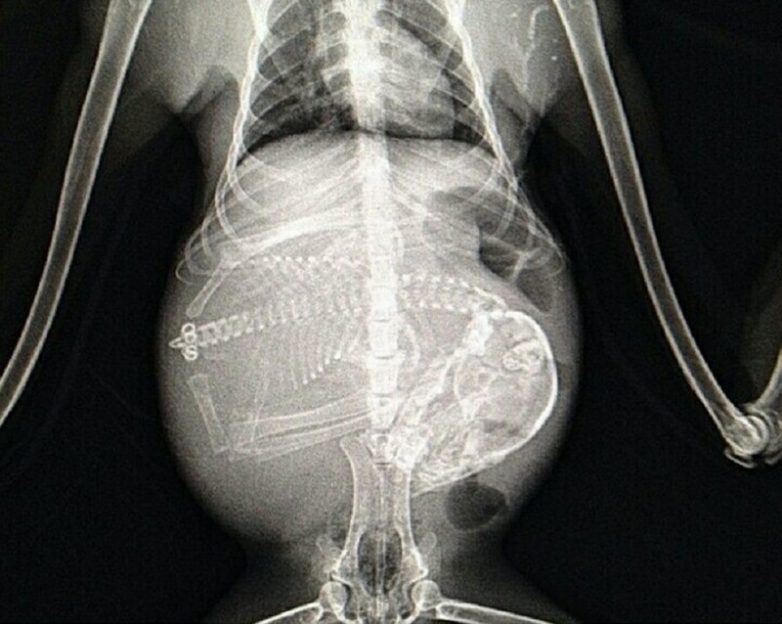

Беременные животные под рентгеном

Так выглядят рентгеновские и ультразвуковые снимки беременных животных.

Беременная обезьяна